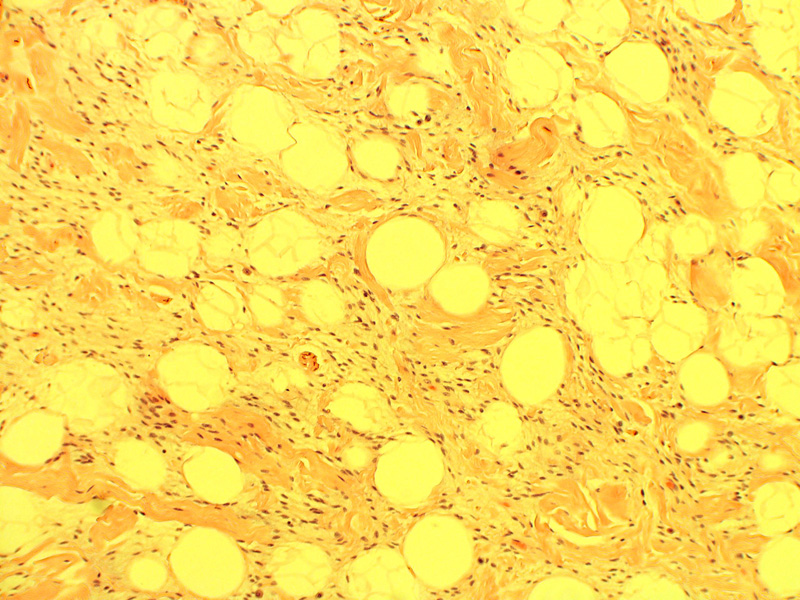

from librepathology.org

Spindle cell lipoma Libre Pathology

Spindle cell lipoma Libre Pathology Spindle Cell Lipoma Radiology To review the evaluation, diagnosis, and treatment of spindle cell lipoma (scl) with emphasis on the location of these. spindle cell lipoma (scl) is a benign adipocytic tumor that primarily occurs in the subcutis of the posterior. Spindle cell lipoma contains a varying mixture of mature adipocytes, bland spindle cells and ropy collagen fibers (cancer. to review the. Spindle Cell Lipoma Radiology.